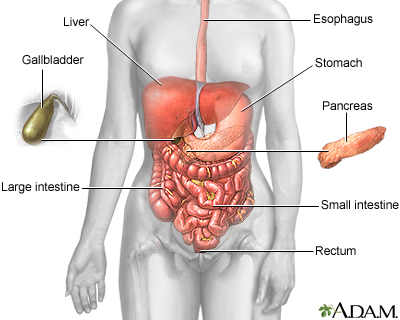

Choledocholithiasis means there is at least one gallstone in the common bile duct. The stone may be made up of bile pigments or calcium and cholesterol salts and are called common bile duct stones.

About 1 in 7 people with gallstones will develop stones in the common bile duct. This is the small tube that carries bile from the gallbladder to the intestine.